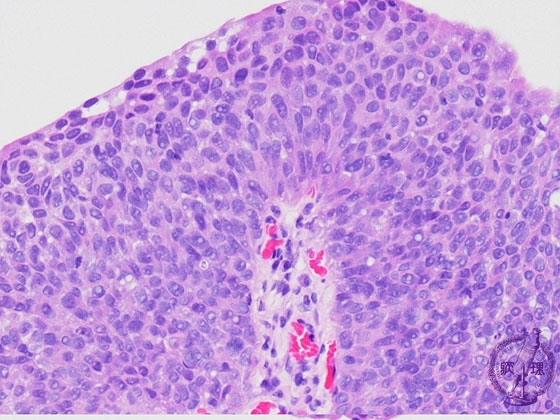

Microscopic findings (HE, high power view): G3, Cancer cells show a high cellularity with high nucleocytoplasmic ratio and hyperchromatism.